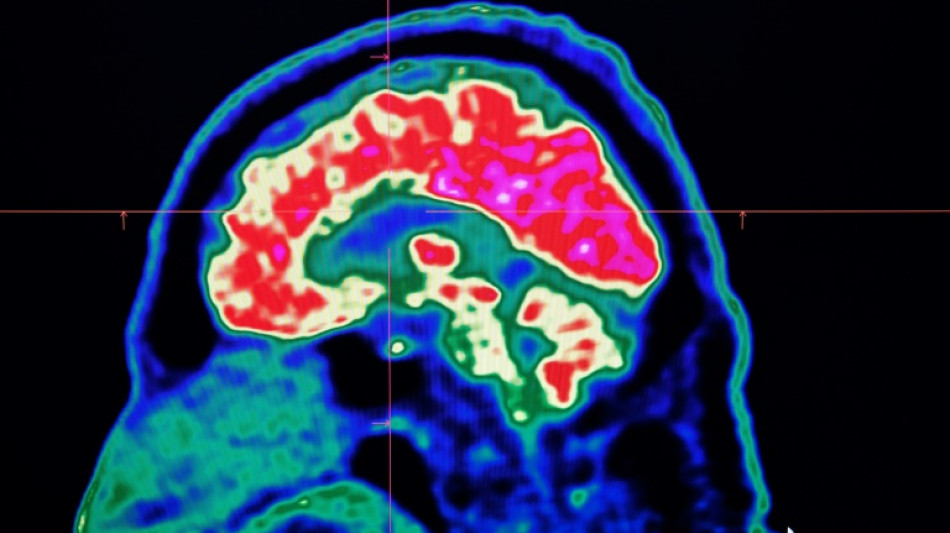

"Décoder" les pensées par l'imagerie cérébrale et l'intelligence artificielle / Photo: Fred TANNEAU - AFP/Archives

Durant l'expérience, trois personnes ont passé 16 heures dans un appareil d'imagerie médicale fonctionnelle (IRMf): cette technique permet d'enregistrer les variations du flux sanguin dans le cerveau, rendant ainsi compte en temps réel de l'activité des zones cérébrales durant certaines tâches (parole, mouvement...).